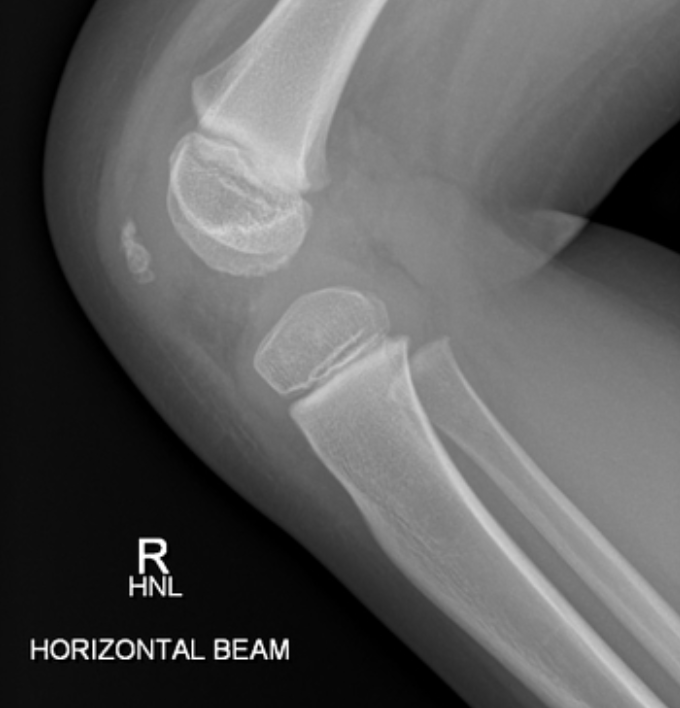

인간은 완전히 형성된 슬개골과 함께 태어나지 않습니다. 대신, 이것은 부드러운 연골(soft cartilage)로 시작되어, 3세경에 뼈화(ossify)가 시작되며, 청소년기까지 완전히 뼈 와 되지 않을 수 있습니다. 아래는 4살 아이의 슬개골인데요, 콩알만 한 것이 보이시나요?

Screenshot 2023-09-25 at 10.55.57 PM.png 4살 아이의 정상 슬개골, https://radiopaedia.org/cases/normal-knee-x-ray-4-year-old-1